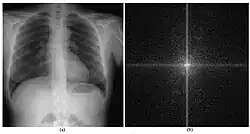

Digitales Röntgen umfasst radiologische Verfahren, bei denen Röntgenbilder nicht mehr auf analogen Röntgenfilmen, sondern digital aufgenommen werden. An Stelle des Films enthalten die Geräte einen Szintillator, der auftreffende Röntgenphotonen entweder in sichtbares Licht oder direkt in Elektrizität umwandelt. Ältere DR-Systeme erfassten die Szintillation der Leuchtschicht optisch verkleinert mit einer Videokamera, einem CCD-Sensor oder CMOS-Chip. Heute setzt man zur Erhöhung der Ortsauflösung Vollfelddetektoren (flat panel detector) ein, die mindestens so groß wie das Röntgenbild sind. Sie enthalten eine Leuchtschicht etwa aus Cäsiumjodid, eine Schicht aus Mikrolinsen, und eine Schicht aus Photodioden. Noch bessere Auflösung haben Festkörperdetektoren aus seltenen Erden wie Gadoliniumoxysulfid oder amorphem Selen, die die auftreffenden Röntgenphotonen ohne Umweg über sichtbares Licht direkt in Elektrizität umwandeln und an die angrenzende TFT-Schicht abgeben. Die im Detektor erfassten Daten werden digital an einen Computer weitergegeben.

Digitales Röntgen hat einen besseren Dichtekontrast, erreicht jedoch nicht die Ortsauflösung des Film-Folien-Röntgens (20 Linienpaare/mm). Bei CR-Systemen ist die Ortsauflösung durch die verwendeten optischen Komponenten auf ca. 2–5 Linienpaare/mm begrenzt[1] (Ausnahme: Fuji-HQ-System für die Mammographie: 11 Lp/mm und Speicherfolienscanner von der Ditabis AG bis 20 LP/mm (bis max. 15 µm)). DR-Systeme reichen von Pixelgrößen um 200 μm[2] bis 50 μm entspr. 10 Lp/mm. Ihre Modulationsübertragungsfunktion ist in der Regel besser als die der CR-Systeme.[3]

Digitales Röntgen ist meist nur im Zusammenspiel mit einem Radiologieinformationssystem (RIS) und einem digitalen Bildarchivierungssystem (PACS) sinnvoll. Die Aufnahmen können im DICOM-Format gespeichert und versendet werden. Im Unterschied zum klassischen Röntgenfilm können die digitalen Bilder problemlos nachbearbeitet werden, z. B. durch Kantenschärfung oder Aufhellung, und die Systeme sind viel weniger gegen Über- und Unterbelichtungen empfindlich, es müssen also weniger Aufnahmen wiederholt werden. Moderne DR-Konsolen analysieren das Schwärzungshistogramm der Aufnahme und korrigieren ggf. die Empfindlichkeit und Steigung der Dichtekurve nachträglich. Artefaktkorrektur, Aufhärtung, und Rauschunterdrückung sind weitere Möglichkeiten zur Bildverbesserung. Unbelichtete Ränder werden automatisch abgeschnitten.